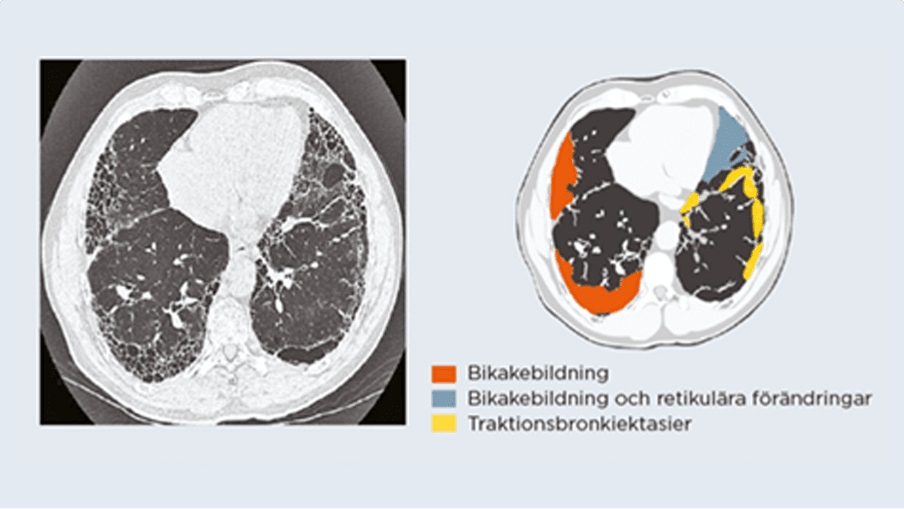

Infärgningarna på den högra bilden speglar fibrosutvecklingen som

syns i datortomografibilden till vänster.

© Lungenfibrosebroschüre / P. Errhalt 2016